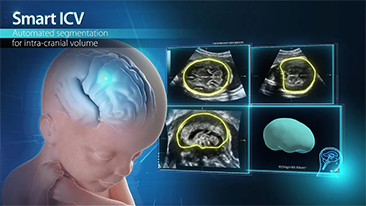

WomenŌĆÖs health is the foundation of health for all and is especially important for countries with aging populations and low fertility levels. MindrayŌĆÖs solution protects multiple life stages, including reproduction, prenatal and intrapartum, and postpartum pelvic floor, with accurate images and efficient and easy-to-use intelligent applications to help caring womenŌĆÖs health in all aspects and cycles.